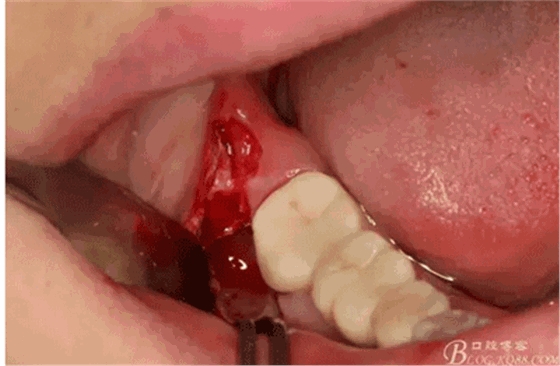

圖8.在頰側(cè)做角形切口

圖10.去骨暴露出48牙冠

圖12.然后再把牙冠近遠(yuǎn)中向縱斷。

圖14.挺松牙根部分

圖15。為了減少去骨,又把牙根橫分成兩塊取出來,這是拔完牙后的牙槽窩情況,我提倡小切口、翻小瓣、少去骨、多分牙原則。目的是為了減輕術(shù)后反應(yīng)。

圖18.大卸八塊的牙齒,之所以分這么多塊,就是為了取這些牙體組織的時候不會碰到前面的47全瓷冠。